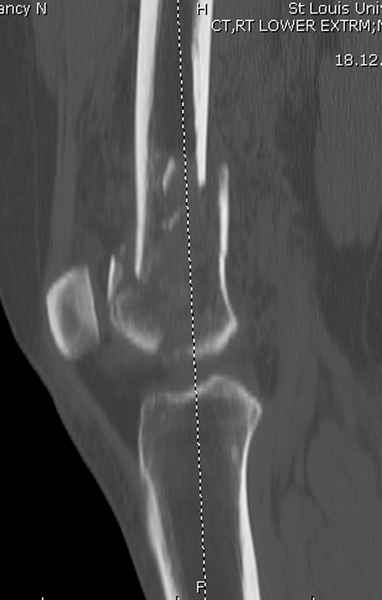

При наличии различных имплантов, любые варианты: слева (полу) открытым - мининвазивным, а справа закрытым интрамедуллярным методом, его считаем более чем приемлемым для фиксации данных переломов.

Проксимальная и дистальная блокировка, независимо от техники введения штифта, ретроградно или антеградно, гарантирует сращение сегментарных переломов бедра без укорочения. Штифты диаметром 12 мм с блокировкой сверху и вниз двумя шурупами выдерживают вес 75 кг больного, что позволяет раннюю профилактику контрактур.

Погоня за "красивой рентгенограммой" не всегда оправдана для фиксации кости, где имеется массивное мягкотканое покрытие. Если так уж хочется исправить положение кости, то при наличии ЭОП, большие костные фрагменты могут быть развернуты или приближены к основному фрагменту методом применения Joystick.

Из-за вариабельности установки дистальных шурупов и возможности перкутанного введения проксимально предпочитаем DePuy Polyax, хотя на сегодняшнем маркете множеств вариантов фиксации дистального бедра перкутанном методом.